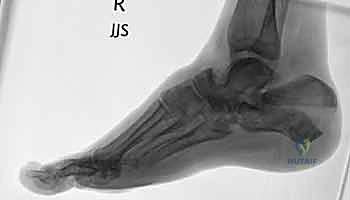

- التصوير بالأشعة السينية (X-rays): لأخذ فكرة أولية عن الكسر (زوايا بوهلر وجيسان - Bohler’s and Gissane’s angles).

- الأشعة المقطعية (CT Scan): وهي الخطوة الأهم والأكثر حيوية. توفر الأشعة المقطعية صوراً ثلاثية الأبعاد وتقاطعاً دقيقاً للكسر، مما يسمح بتصنيف الكسر (نظام ساندرز - Sanders Classification) وتحديد عدد الشظايا العظمية ومدى انزياحها داخل المفصل. بناءً على هذه الأشعة، يضع الدكتور هطيف خطته الجراحية الدقيقة.